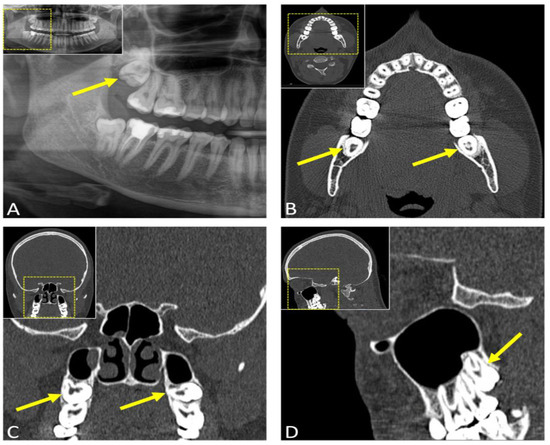

- Nakamori, K.; Tomihara, K.; Noguchi, M. Clinical significance of computed tomography assessment for third molar surgery. World J. Radiol. 2014, 6, 417–423. [Google Scholar] [CrossRef]

- Susarla, S.M.; Dodson, T.B. Preoperative computed tomography imaging in the management of impacted mandibular third molars. J. Oral Maxillofac. Surg. 2007, 65, 83–88. [Google Scholar] [CrossRef]

- Xu, G.Z.; Yang, C.; Fan, X.D.; Yu, C.Q.; Cai, X.Y.; Wang, Y.; He, D. Anatomic relationship between impacted third mandibular molar and the mandibular canal as the risk factor of inferior alveolar nerve injury. Br. J. Oral Maxillofac. Surg. 2013, 51, e215–e219. [Google Scholar] [CrossRef] [PubMed]